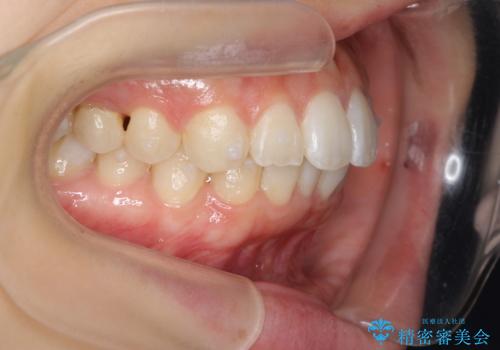

前歯のがたつき インビザラインで

- 前歯のがたつきを治したいとのことでした。歯を抜かずにできる範囲で引っ込めたいとのことでした。

歯列の側方拡大(横に広げる)と、エナメル質の削合で並べました。

歯を抜いているわけではないので、口元はそこまで変化はありませんが、前に出すことなくデコボコは取れたと思います。